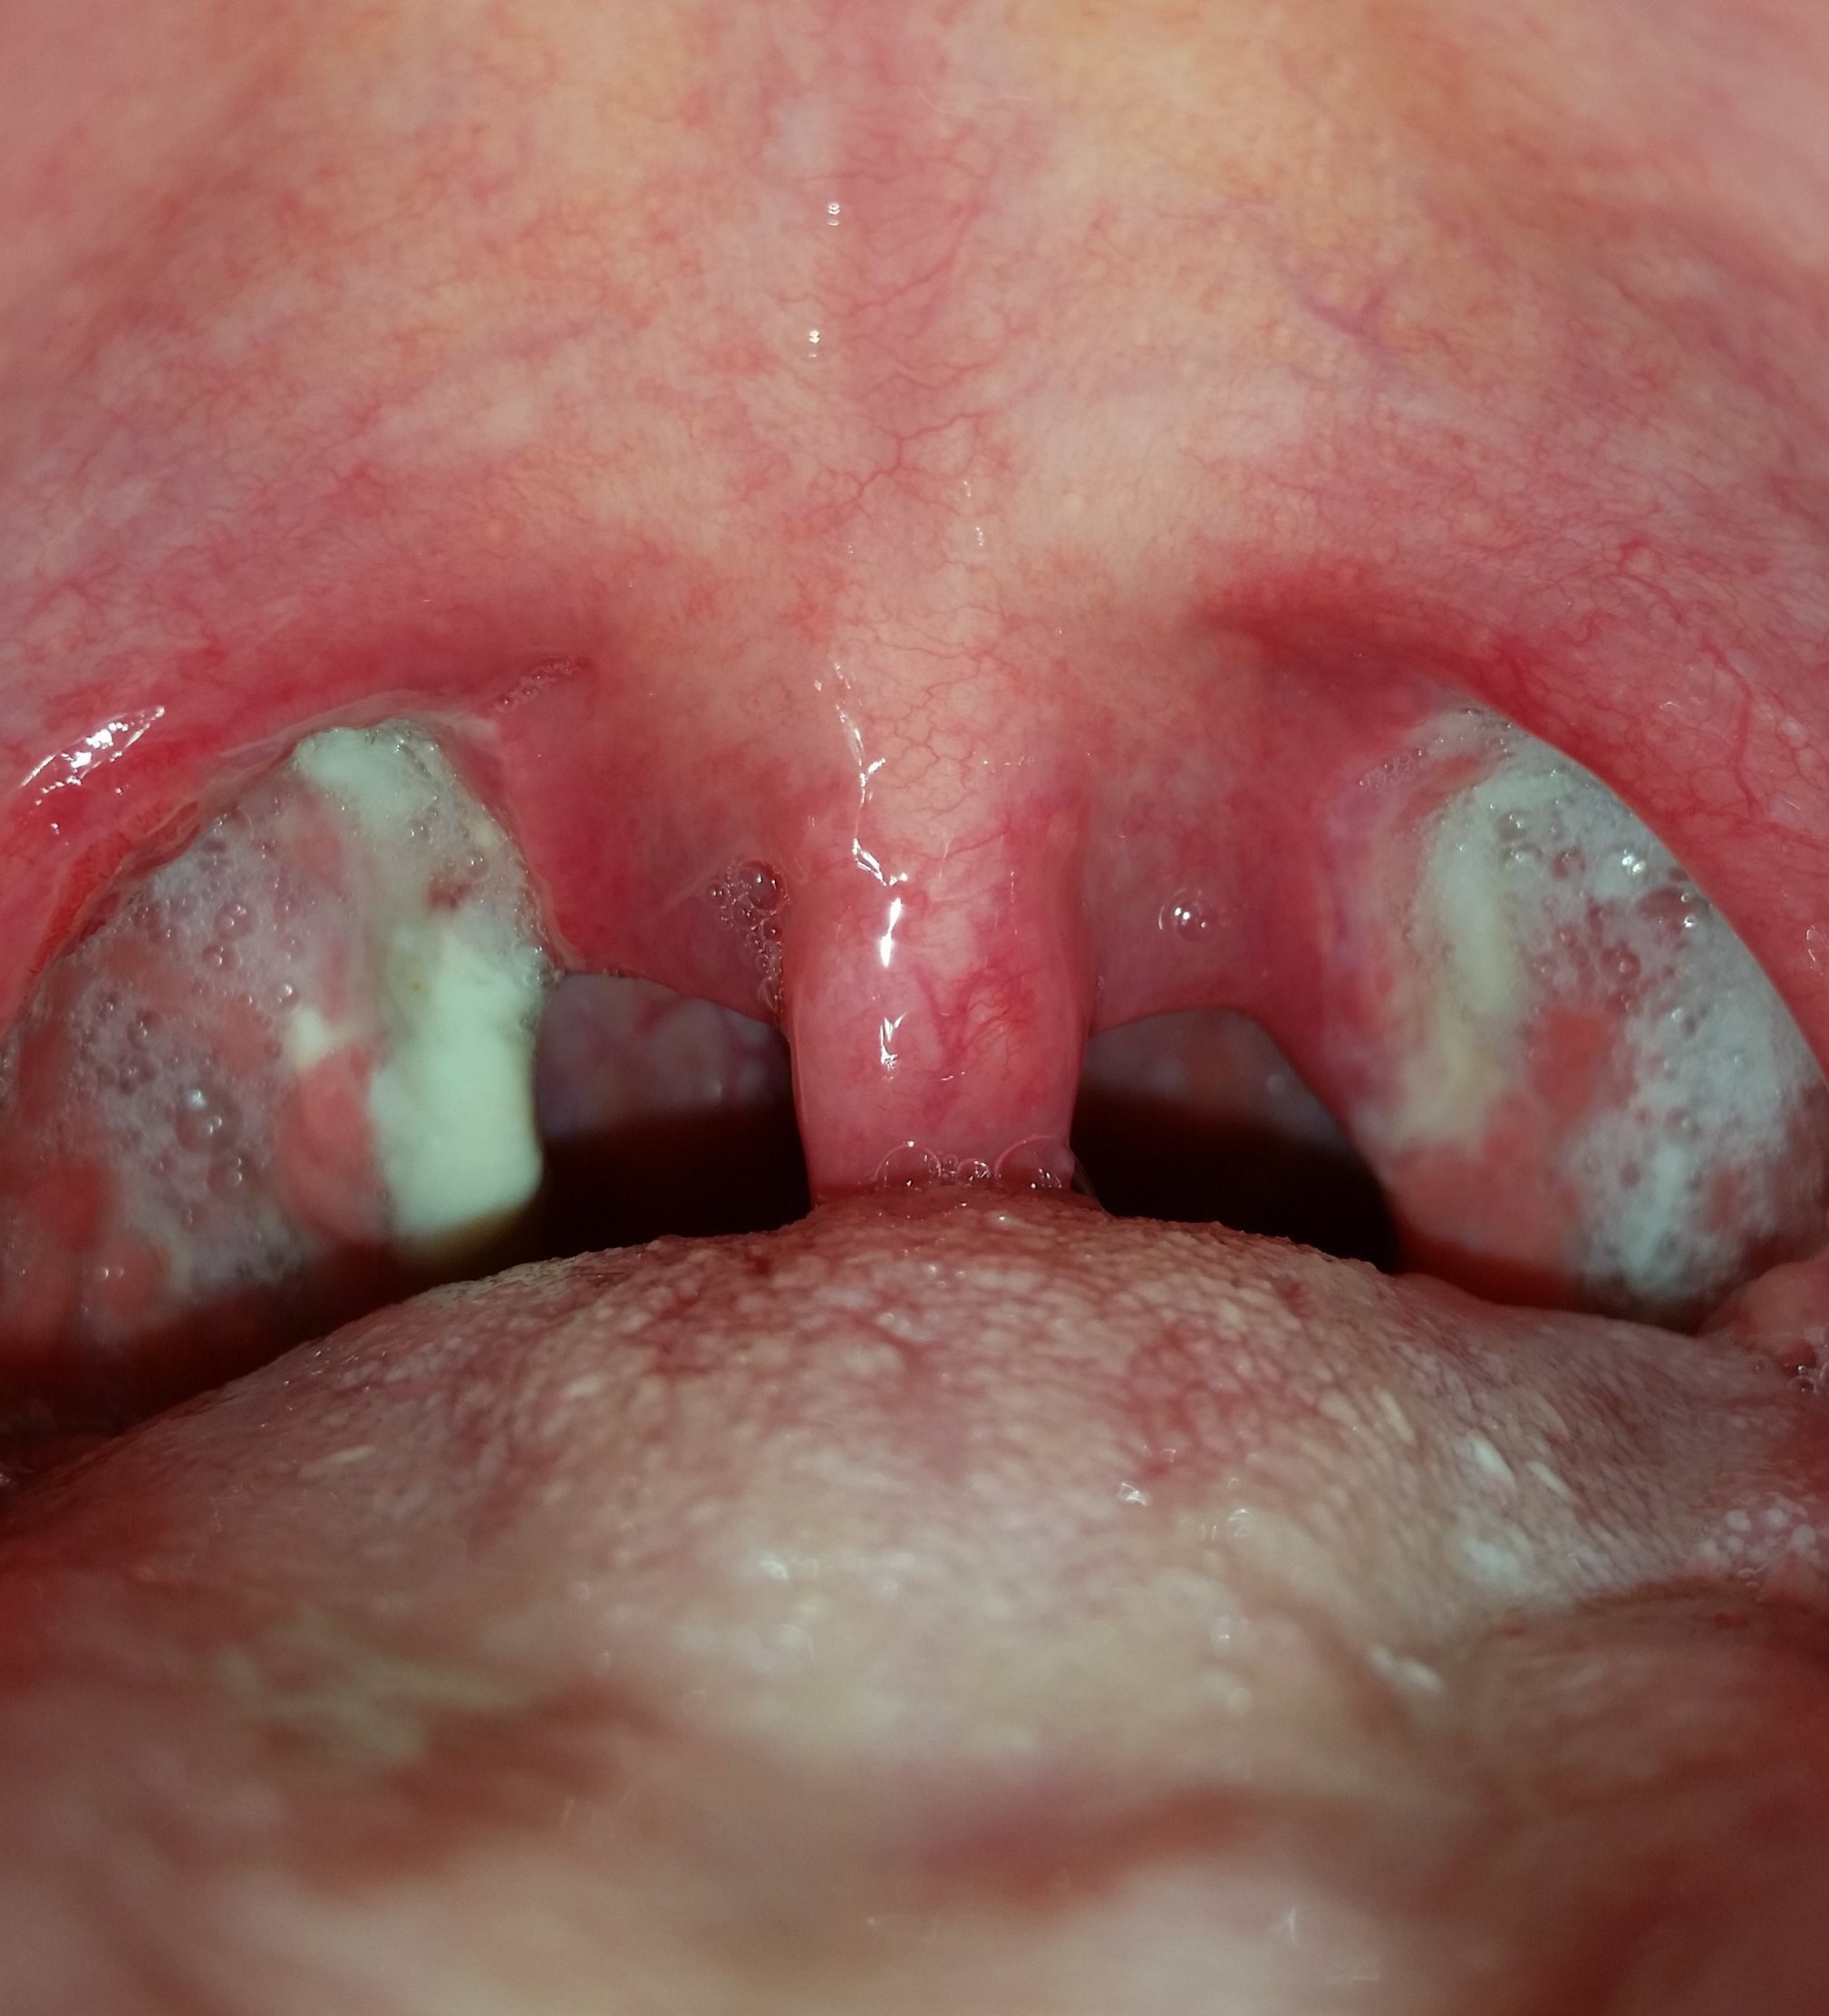

Mandel OP – Bilder Dokumentation Heilungsprozess

- Mandeloperation Tag 2

Nach der Operation bildeten sich direkt die weiß, grünlichen Beläge (Fibrinbeläge).

Ab dem Tag 9 lösten sich langsam die Beläge. (Ein ziemlich brennendes Gefühl)